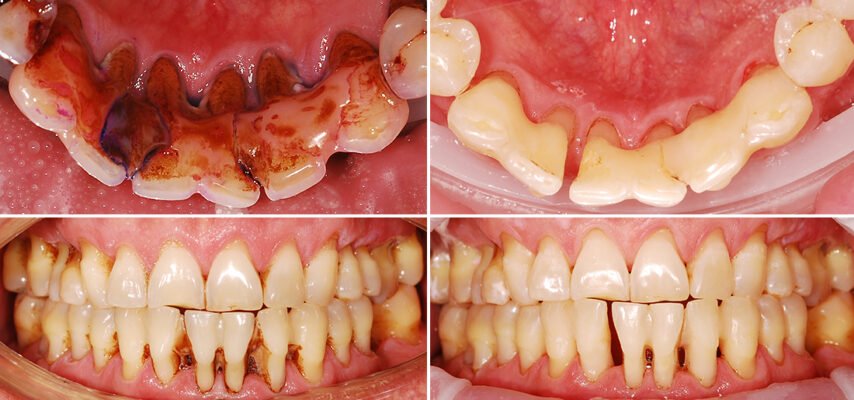

- Кровоточивість ясен: особливо при чищенні зубів або вживанні твердої їжі.

- Чутливість: зуби раптом реагують на холодне, гаряче, кисле.

- Зміна кольору ясен: від блідо-рожевого до червоного або навіть синюшного.

- Пародонтит: інфекція, яка атакує ваші ясна. Дістає в глибині, вириваючи з коренем.